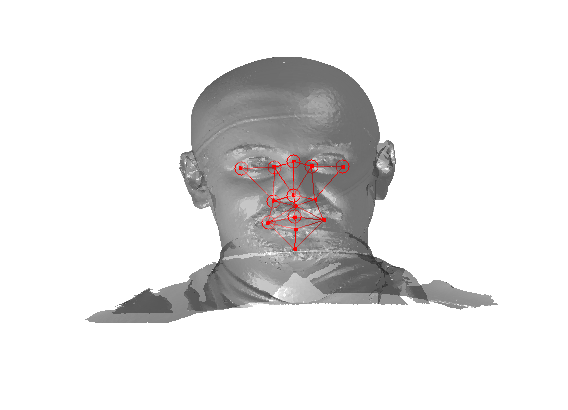

The landmarking system that we have implemented is a modified version of Creusot et al [23], where landmark candidates are generated via per-landmark scoring functions and then a configural model is iteratively fitted using a sample-consensus scheme. There are two parts to this algorithm: an off-line training scheme, shown in Fig. 5 and an online landmarking scheme, shown in 6. Note that we consider a sparse model of the face to consist of a set of landmarks in paticular configuration along with a set of landmark detector functions that score the likelihood of a particular vertex being a particular landmark, based on its local shape.

Referring to Fig. 5, our method is a supervised learning technique - landmarks are marked by hand on a set of training images. We used 279 faces (each different individuals) in the Face Recognition Grand Challenge (FRGC) dataset [26]. The landmarks used are described in table 1 111Some descriptions taken from www.facebase.org and can be seen on an example FRGC 3D face scan in Fig. 7.

Fig. 9 shows examples of the fitted model (trained on FRGC data) on the first four subjects in our Headspace training set. Note that the mean of the landmarks in the sparse model is centred on the orgin, and so the scan data is moved towards that and becomes frontal in pose. We note that other researchers [28] have used 3D landmark localisation to find the head, but often this only includes landmarks that are relatively easy to localise, namely inner eye corners and nose. Localising more landmarks over a wider facial area has a number of advantage in terms of cropping, pose normalisation and global 3D template warping, all of which are described later.